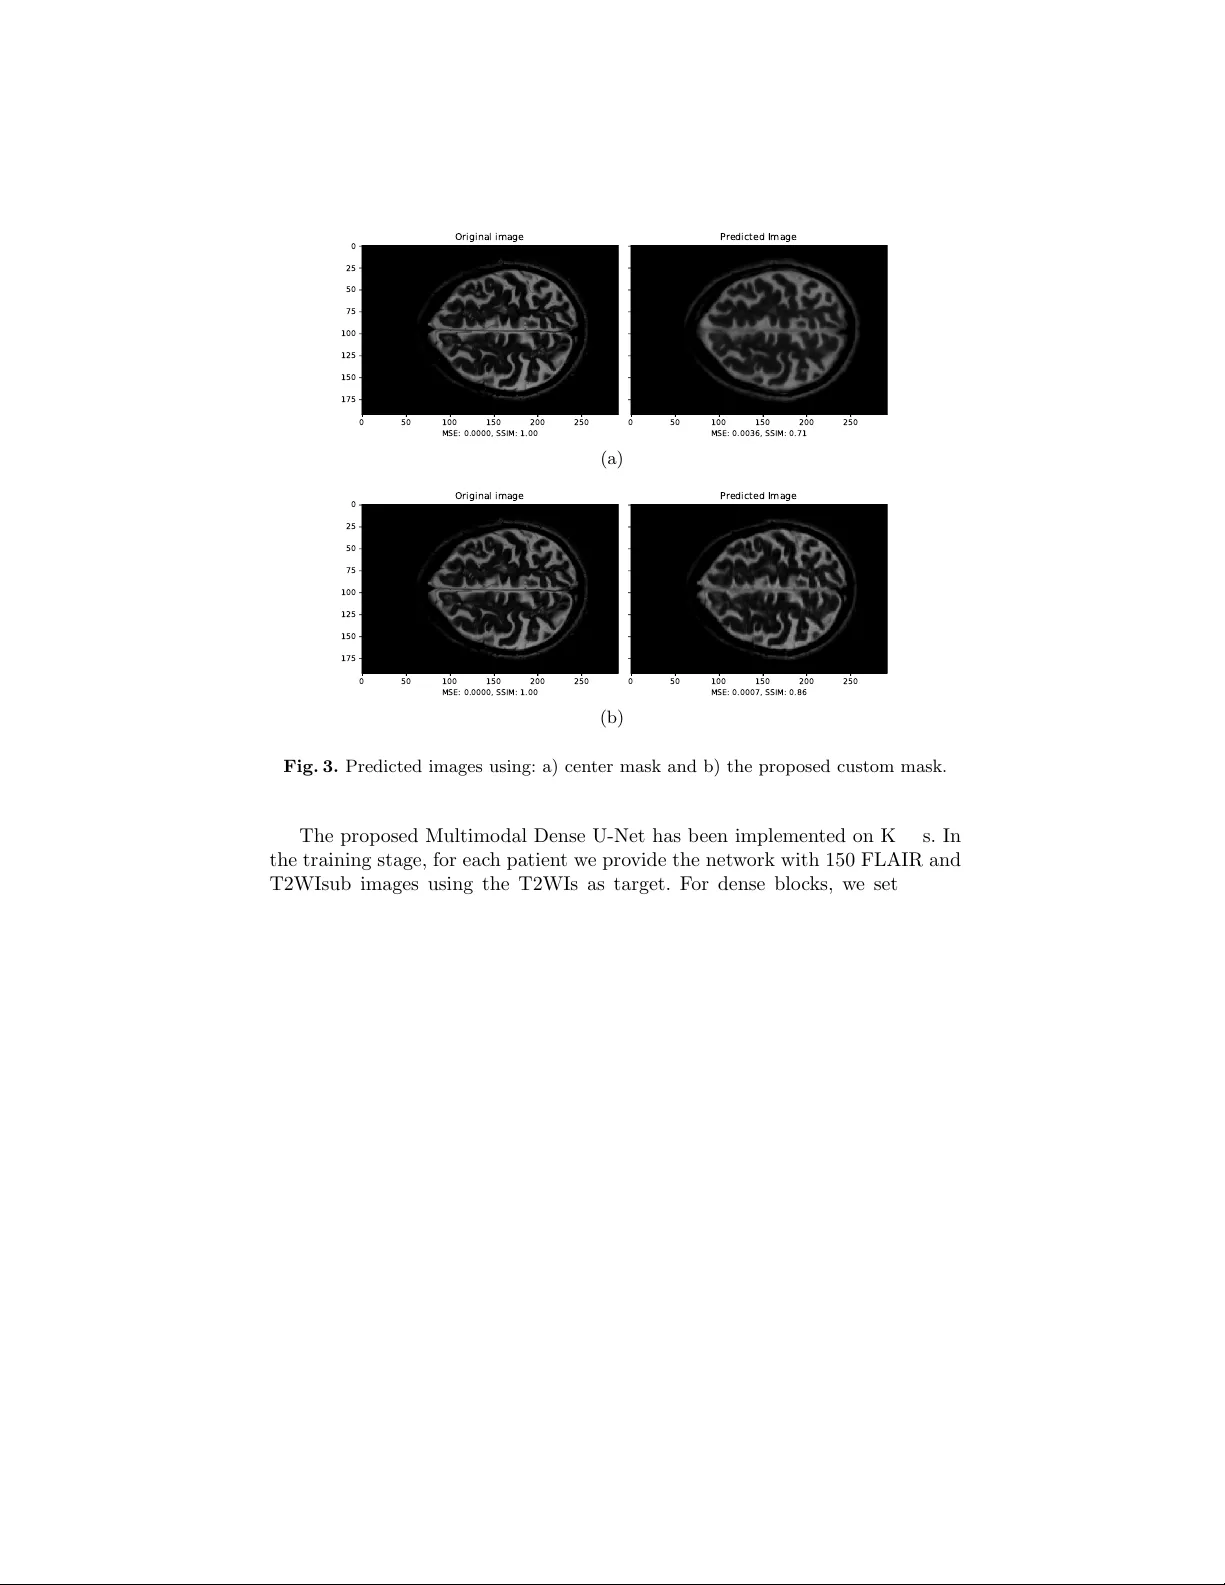

A Multimo dal Deep Net w ork for the Reconstruction of T2W MR Images An tonio F alv o, Danilo Comminiello, Simone Scardapane, Mic hele Scarpiniti, and Aurelio Uncini Dept. Information Eng., Electronics and T elecommunications (DIET) Sapienza Universit y of Rome, Via Eudossiana 18, 00184 Rome, Italy danilo.comminiello@uniroma1.it Abstract. Multiple sclerosis is one of the most common c hronic neuro- logical diseases affecting the cen tral nerv ous system. Lesions produced b y the MS can b e observ ed through tw o modalities of magnetic resonance (MR), kno wn as T2W and FLAIR sequences, b oth providing useful infor- mation for form ulating a diagnosis. How ever, long acquisition time makes the acquired MR image vulnerable to motion artifacts. This leads to the need of accelerating the execution of the MR analysis. In this pap er, we presen t a deep learning metho d that is able to reconstruct subsampled MR images obtained by reducing the k -space data, while maintaining a high image quality that can b e used to observe brain lesions. The pro- p osed metho d exploits the multimodal approach of neural netw orks and it also fo cuses on the data acquisition and processing stages to reduce execution time of the MR analysis. Results pro ve the effectiv eness of the prop osed metho d in reconstructing subsampled MR images while sa ving execution time. Keyw ords: magnetic resonance imaging, fast MRI, m ultiple sclerosis, deep neural netw ork 1 In tro duction Nuclear magnetic resonance (NMR) is a transmission analysis tec hnique that allo ws to obtain information on the state of matter, exploiting the in teraction b et w een magnetic fields and atoms n uclei. In the biomedical field, information deriving from the NMR is represen ted in the form of tomographic images. No wa- da ys, the NMR plays an imp ortan t role in the health field, and it allows to carry out a whole typology of diagnostic exams, from traditional to functional neuro- radiology , from in ternal diagnostic to obstetrics and p ediatric diagnostics [1]. During the acquisition stage of an MR signal, it is necessary to sample the en tire k -space to obtain images that are as m uch detailed as possible [4, 10]. Data in the k -space enco de information on spatial frequencies and are generally captured line by line. Therefore, the acquisition time for a given sequence de- p ends on the n umber of lines sampled in the k -space, th us leading to a rather slo w acquisition pro cess. Moreov er, significan t artifacts ma y o ccur in the MR 2 F alvo et al. images caused by to slow mov ements of the patien t, due to physiological factors or to fatigue, e.g., to o muc h time in the same p osition [4, 10]. Moreov er, the long scan time also increases the healthcare cost for the patient, b esides limiting the a v ailability of MR scanners. Ov er the years, several metho ds, suc h as compressed magnetic resonance and parallel magnetic resonance [3, 7, 11, 12], ha ve b een proposed to accelerate MRI scans b y skipping the k -space phase co ding lines and a void the aliasing phenomenon introduced by subsampling. The problem of accelerating magnetic resonance can also be tackled through deep learning tec hniques. In particular, the reconstruction of tomographic images has been often efficiently addressed b y using conv olutional neural netw orks (CNNs) [8, 13, 14, 16, 17]. Most of the state-of-the-art metho ds fo cus on the reconstruction of MR im- ages using a unimodal neural architecture where a subsampled image to b e reconstructed is pro vided as input. In this pap er, w e prop ose a new deep learn- ing metho d for reconstructing MR images by exploiting additional information pro vided b y FLAIR images. Such images are widely used in the MR diagnosis as they allow to enhance the brain lesions due to the disease. FLAIR images are highly correlated with the T2 w eighted images (T2WIs), thus the joint use of such images increases the efficiency of the reconstruction and also presents m uch more information in the lesion region. T o exploit b oth the images, we pro- p ose a m ultimo dal deep neural netw ork, inspired by the w ell-kno wn U-Net, a con volutional-based mo del that w as dev elop ed for biomedical image segmenta- tion [15]. In the l iterature, sev eral studies hav e b een prop osed using a multimodal approac h for image reconstruction. In [19], T2WIs were attempt to b e estimated from T1WI, while other w orks fo cus on impro ving the quality of the subsam- pled images with the help of high resolution images with different contrast [6, 9]. Ho wev er, to the b est of our knowledge, no attempt has ever b een made to re- construct T2WIs from subsampled T2WIs (T2WIsub) and FLAIR images while main taining high image qualit y in the area of lesions. Exp erimen tal results prov e that the proposed method is able to accelerate the MR analysis four times, while preserving the image qualit y , with a high detail of any lesion and negligible aliasing artifacts. The rest of the pap er is organized as follows. In Section 2, we introduce the prop osed approac h, including a new subsampling mask, while the prop osed Multimo dal Dense U-Net is presented in Section 3. Results are shown in Section 4 and, finally , our conclusion is drawn in Section 5. 2 Prop osed Approac h: Main Definitions W e first fo cus on the images to b e pro vided as input in order to reconstruct the T2WI. 2.1 Problem F orm ulation W e denote with X T 2 the k -space for the T2WI that represen ts the target. Mul- tiplying the k -space X T 2 for a suitably designed mask M , it is p ossible to obtain Multimo dal Deep Netw ork 3 a subsampled v ersion of the k -space, i.e., X T 2 sub = M · X T 2 (1) The bidimensional inv erse F ourier transform allows to achiev e data in to the space domain. Therefore, we define the fully-sampled target image Y T 2 and the subsampled T2 image Y T 2 sub to be used for reconstruction through the proposed deep netw ork. Finally , we denote the FLAIR image to b e provided as input with Y F . W e w ant to reconstruct the fully-sampled T2 image Y T 2 , giv en the only a v ailability of subsampled Y T 2 sub and Y F . The reconstructed T2 image is denoted as ˆ Y T 2 . T o this end, w e build and train a deep netw ork to minimize the following loss function: arg min { MSE + DSSIM } (2) in whic h the MSE denotes the mean-square error and DSSIM the structural dissimilarit y index. The former is defined as: MSE = 1 N N X i =1  Y T 2 ,i − ˆ Y T 2 ,i  2 . (3) On the other hand, the DSSIM is complementary to the structural similarity index (SSIM), whic h is often adopted to assess the p erceiv ed qualit y of television and film images as well as other types of digital images and videos. It was designed to improv e traditional metho ds such as the signal-to-p eak noise ratio (PSNR) and the mean square error (MSE), and it is defined as: DSSIM  Y T 2 , ˆ Y T 2  = 1 2 −  2 µ Y µ ˆ Y + c 1   2 σ Y ˆ Y + c 2  2  µ 2 Y + µ 2 ˆ Y + c 1   σ 2 Y + σ 2 ˆ Y + c 2  (4) where µ Y , µ ˆ Y represen t the mean v alues, σ 2 Y and σ 2 ˆ Y the v ariances, and σ Y ˆ Y the co v ariance. 2.2 Customization of a New Subsampling Mask Most of the existing literature dealing with MRI acceleration mainly focuses on the reconstruction of images. How ever, the quality of the reconstruction dep ends significan tly on ho w k -space is sampled. This problem can b e faced essentially by adopting one of the following approaches: 1) a dynamic appr o ach based on deep learning in which cells of fixed width are allo wed to mov e in the k -space and c hange p osition based on the reconstruction performance; 2) a static appr o ach in whic h fixed sampling masks are used that go to select only certain areas of the k -space. In this work, we choose the static approach since the dynamic one do es not guaran tee that the p ow er sp ectrum of a reference image is similar to that of the test image. The adopted sampling method consists of a mask that acts along 4 F alvo et al. Kx 50 100 150 200 250 Ky 20 40 60 80 100 120 140 160 180 (a) Kx 50 100 150 200 250 Ky 20 40 60 80 100 120 140 160 180 (b) Fig. 1. Subsampling masks: a) center mask and b) the prop osed custom mask. the direction of the phase co ding of the k -space, in whic h it is p ossible, once the subsampling factor is set, to c ho ose the p ercen tage of samples that will o ccup y the central part of k -space, thus leaving the rest of the samples equidistant from eac h other. Figure 1 shows tw o different types of mask b oth obtained by setting a subsam- pling factor k = 4. In the center mask of Fig. 1(a), samples are taken exclusively in the central area of the k -space, where most of the low-frequency comp onents can b e found pro viding useful information on the contrast of the image [19]. Ho wev er, in this w ork, we prop ose a new mask, depicted in Fig. 1(b), which selects the 80% of the total samples from the center and the remainder in an equidistan t manner so as to ha ve information even in the high frequencies. 3 Multimo dal Dense U-Net The prop osed neural net work is multimodal architecture: on one branc h we pro- vide the T2WIsub as input while on the other branc h we provide the FLAIR image to be used to impro ve the reconstruction quality . W e exp ect all the spatial information in the FLAIR image to help estimate the anatomical structures in T2WI. Both inputs initially undergo separate con traction transformations to then merge later and follow the classic coding-deco ding approach of U-Net models. The prop osed Multimo dal Dense U-Net is depicted in Fig. 2. The netw ork consists essentially of 4 comp onen ts, namely conv olutive la yers, p ooling lay ers, decon volutiv e la y ers and dense blo c ks. The size of the charac- teristic map decreases along the contraction path through the p ooling blo c ks as it increases along the expansion path by decon v olution. Pooling partitions the input image into a set of squares, and for eac h of the resulting regions re- turns the maxim um v alue as output. Its purp ose is to progressively reduce the size of the representations, so as to reduce the num b er of parameters and the computational complexit y of the netw ork, at the same time counteracting any o verfitting. Multimo dal Deep Netw ork 5 C O N V O L U T I O N 3 X 3 P O O L I N G 2 X 2 D E C O N V O L U T I O N 2 X 2 C O N C A T E N A T E M E R G E P O O L I N G F E A T U R E S C O N V . F E A T U R E S D E C O N V . F E A T U R E S D E N S E B L O C K 6 4 T 2 W I _ s u b F L A I R T 2 W I C O N V 1 6 4 6 4 6 4 6 4 6 4 6 4 6 4 6 4 6 4 6 4 6 4 Fig. 2. Scheme of the prop osed Multimo dal Dense U-Net architecture. Decon volutiv e la y ers act inv ersely with respect to p o oling and aim to increase the spatial dimensions of the inputs. This allows to obtain images of a size com- parable to those of the input images from the net w ork. In the simplest case these lev els can b e implemented as static ov ersampling with bilinear interpolation. The dense block, prop osed in [5], allo ws to effectiv ely increase the depth of the entire netw ork while main taining a low complexity . Moreo ver, it requires less parameters to b e trained. The dense blo c k consists of three consecutiv e op erations: batc h normalization (BN) , ELUs activ ation functions [2] and 3 × 3 con volution filters. The hyper-parameters for the dense blo ck are the gro wth rate (GR) and the n umber of con volutional la yers (NC). The netw ork ends with a reconstruction level consisting of a dense blo c k follow ed by a 1 × 1 conv olutional la yer that yields the reconstructed T2WI. 4 Exp erimen tal Results 4.1 Dataset and Netw ork Setting W e test the prop osed net work on a dataset con taining MRIs of m ultiple sclerosis patien ts [18]. In particular, the dataset is related to 30 patients and it con tains axial 2D-T1W, 2D-T2W and 3D-FLAIR images. The final v oxel size of suc h images is 0 . 46 × 0 . 46 × 0 . 8 mm 3 . In our work, a further prepro cessing has b een p erformed in MA TLAB to make the vo xel size isotropic to 0 . 8 × 0 . 8 × 0 . 8 mm 3 , to extract slices of size 192 × 292, and to shrink in tensity to the range [0 , 1]. T2WIsub images were created by considering tw o types of masks, the center mask and the prop osed custom mask, with a subsampling factor k = 4. 6 F alvo et al. 0 50 100 150 200 250 MSE: 0.0000, SSIM: 1.00 0 25 50 75 100 125 150 175 Original image 0 50 100 150 200 250 MSE: 0.0036, SSIM: 0.71 Predicted Image (a) 0 50 100 150 200 250 MSE: 0.0000, SSIM: 1.00 0 25 50 75 100 125 150 175 Original image 0 50 100 150 200 250 MSE: 0.0007, SSIM: 0.86 Predicted Image (b) Fig. 3. Predicted images using: a) cen ter mask and b) the prop osed custom mask. The prop osed Multimo dal Dense U-Net has b een implemented on Keras. In the training stage, for each patient w e provide the netw ork with 150 FLAIR and T2WIsub images using the T2WIs as target. F or dense blo c ks, we set a zero gro wth rate and a num b er of levels equal to 5 with feature maps size of 64 and ELU activ ation lev els. W e use Adam as an optimizer for training. A total of 80 ep ochs are p erformed, with early stopping. The duration of each ep och is ab out 15 minutes, having set a batch size of 4 and using a desktop PC with an In tel Core i5 6600-K 3.50 GHz CPU, 16 GB of RAM and NVIDIA GeF orce GTX 970 GPU. T o quan titatively ev aluate reconstruction p erformance, w e use the MSE and DSSIM metrics. 4.2 Ev aluation of the Proposed Mask W e wan t to ev aluate first the effectiveness of the prop osed custom subsampling mask compared to the center mask on the quality of reconstruction in terms of the SSIM using a Dense U-Net net work. Results are shown in Fig. 3, where it is clear that the prop osed custom mask allo ws us to obtain a reconstruction of the image with outstanding p erformance. In particular, using the cen ter mask we get a 71% reconstruction p ercen tage com- pared to the target (Fig. 3(a)), while using the proposed custom mask (Fig. 3(b)) the similarity index rises up to 86%. Multimo dal Deep Netw ork 7 Fig. 4. Predicted T2WI reconstructed by the prop osed Multimo dal Dense U-Net. 0 20000 40000 60000 80000 100000 Iteration 10 − 1 10 0 Loss Fig. 5. Loss function b eha vior. 4.3 Ev aluation of the Proposed Deep Arc hitecture Conceptually , the prop osed arc hitecture and the standard Dense U-Net might app ear similar, but the former one manages the tw o inputs differently . Moreo ver, the h yp er-parameters of the dense blo c ks chosen for our netw ork considerably c hange the concept of dense blo ck as the whole of gro wth was set to zero thus a voiding internal expansion in dense blo c ks. W e compare the reconstruction quality of the tw o netw orks in terms of SSIM ha ving used the mask that provided the best p erformance for the subsampling, i.e., the prop osed custom mask. Results are shown in Fig. 4, where it is clear that the quality of reconstruction has been considerably impro ved compared to Dense U-Net. In particular, the degree of similarity with resp ect to the target is 94% rather than 86% of the Dense U-Net. By using the prop osed arc hitecture, high image qualit y is achiev ed, thus enabling the recognition of brain injuries caused by the disease. W e also show the loss function b eha vior for the prop osed metho d in Fig. 5. 8 F alvo et al. 5 Conclusion In this w ork, we prop ose a deep learning model exploiting the capabilities of b oth m ultimo dal netw orks and dense blocks. In particular, the prop osed approach allo ws to reconstruct T2WIs, subsampled by a factor of 4, thus leveraging the correlation that exists with FLAIR images. At the same time, the prop osed metho d is able to maintain a high quality of image reconstruction, in particular in the area of the brain lesions due to multiple sclerosis. The comparison with a state-of-the-art Dense U-Net architecture has shown that the prop osed netw ork outp erforms both in terms of p erceptiv e quality and in terms of execution times. F uture w orks will fo cus on increasing the sp eed of the MRI scan, with the goal of achieving an acceleration of at least 10 times, and on further impro ving the reconstruction quality . References 1. Beall, P .T., Amtey , S.R., Kasturi, S.R.: NMR Data Handbo ok for Biomedical Ap- plications. Pergamon Bo oks Inc., Elmsford, NY (1984) 2. Clev ert, D.A., Unterthiner, T., Ho c hreiter, S.: F ast and accurate deep netw ork learning by exp onen tial linear units (ELUs). In: In ternational Conference on Learn- ing Representations (ICLR). pp. 1–14. San Juan, Puerto Rico (Ma y 2016) 3. Gamp er, U., Boesiger, P ., Kozerke, S.: Compressed sensing in dynamic MRI. Mag- netic Resonance in Medicine 59(2), 365–373 (F eb 2008) 4. Haac ke, E.M., Bro wn, R.W., Thompson, M.R., V enk atesan, R.: Magnetic Reso- nance Imaging: Physical Principles and Sequence Design, v ol. 82. Wiley-Liss, New Y ork, NY (1999) 5. Huang, G., Liu, Z., v an der Maaten, L., W ein b erger, K.Q.: Densely connected con volutional net works. In: IEEE Conference on Computer Vision and P attern Recognition (CVPR). pp. 2261–2269. Honolulu, HI (Jul 2017) 6. Huang, J., Chen, C., Axel, L.: F ast multi-con trast MRI reconstruction. Magnetic Resonance Imaging 32(10), 1344–1352 (Dec 2014) 7. Jaspan, O.N., Fleysher, R., Lipton, M.L.: Compressed sensing MRI: A review of the clinical literature. The British Journal of Radiology 88(1056) (Dec 2015) 8. Jin, K.H., McCann, M.T., F roustey , E., Unser, M.: Deep conv olutional neural net- w ork for inv erse problems in imaging. IEEE T ransactions on Image Pro cessing 26(9), 4509–4522 (Sep 2017) 9. Kim, K.H., Do, W.J., Park, S.H.: Impro ving resolution of MR images with an adv ersarial netw ork incorp orating images with different contrast. Medical Physics 45(7), 3120–3131 (Jul 2018) 10. Liang, Z.P ., Lauterbur, P .C.: Principles of Magnetic Resonance Imaging. A Signal Pro cessing Perspective. The Institute of electrical and Electronics Engineers, New Y ork, NY (2000) 11. Lustig, M., Donoho, D., Pauly , J.M.: Sparse MRI: The application of compressed sensing for rapid MR imaging. Magnetic Resonance in Medicine 58, 1182–1195 (Oct 2007) 12. Lustig, M., Donoho, D.L., Santos, J.M., P auly , J.M.: Compressed sensing MRI. IEEE Signal Pro cessing Magazine 25(2), 72–82 (Mar 2008) Multimo dal Deep Netw ork 9 13. McCann, M.T., Jin, K.H., Unser, M.: Conv olutional neural netw orks for in verse problems in imaging: A review. IEEE Signal Pro cessing Magazine 34(6), 85–95 (No v 2017) 14. Qin, C., Schlemper, J., Caballero, J., Price, A.N., Ha jnal, J.V., Rueck ert, D.: Con- v olutional recurrent neural netw orks for dynamic MR image reconstruction. IEEE T ransactions on Medical Imaging 38(1), 280–290 (Jan 2019) 15. Ronnen b erger, O., Fischer, P ., Bro x, T.: U-Net: Conv olutional netw orks for biomedical image segmentation. In: International Conference on Medical Image Computing and Computer-Assisted In terven tion (MICCAI). Lecture Notes in Computer Science, vol. 9351, pp. 234–241. Springer, Cham (2015) 16. Ro y , S., Butman, J.A., Reic h, D.S., Calabresi, P .A., Pham, D.L.: Multiple sclerosis lesion segmentation from brain MRI via fully con volutional neural net works. arXiv preprin t arXiv:1803.09172v1 (Mar 2018) 17. Sc hlemp er, J., Caballero, J., Ha jnal, J.V., Price, A.N., Rueck ert, D.: A deep cas- cade of conv olutional neural netw orks for dynamic MR image reconstruction. IEEE T ransactions on Medical Imaging 37(2), 491–503 (F eb 2018) 18. ˇ Ziga, L., Galimzianov a, A., Koren, A., Lukin, M., Pern u ˇ s, F., Lik ar, B., ˇ Spiclin, v.: A nov el public MR image dataset of multiple sclerosis patients with lesion segmen tations based on m ulti-rater consensus. Neuroinformatics 16(1), 51–63 (Jan 2018) 19. Xiang, L., Chen, Y., Chang, W., Zhan, Y., Lin, W., W ang, Q., Shen, D.: Deep leaning based multi-modal fusion for fast MR reconstruction. IEEE T ransactions on Biomedical Engineering (Early Access) (2018)

Original Paper

Loading high-quality paper...